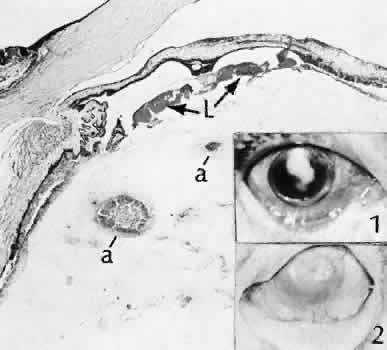

Iris cyst formation (Figs. 45 and 46 is also caused by implantation of surface epithelium onto the iris at the time of surgery or trauma. The cyst generally grows slowly and is accompanied by peripheral anterior synechiae. If extensive, the cysts may cause a secondary chronic closed-angle glaucoma. Histologically, the cyst is lined by stratified squamous or columnar epithelium, sometimes containing mucous cells, and is filled with keratin debris (white or pearly cysts) or mucous fluid (clear cysts).

Fig. 45. Two cases of epithelial iris cyst formation following cataract extraction. A. Instead of forming a flat sheet to cover the posterior cornea and the anterior iris, the invading epithelium has formed a cyst in the anterior chamber. The cyst usually retains some continuity with the original wound but also may become free-floating in the anterior chamber. B. In this case, there is extensive distortion of the iris. The type of ingrowth, sheet or cystic, is a major determinant of the method of treatment used. C. The histologic character of the cyst lining indicates the presence of goblet cells. The origin of these cells may have been from the conjunctiva. In this rare circumstance, the cyst may become filled with mucous. (Hematoxylin-eosin stain; × 101.)